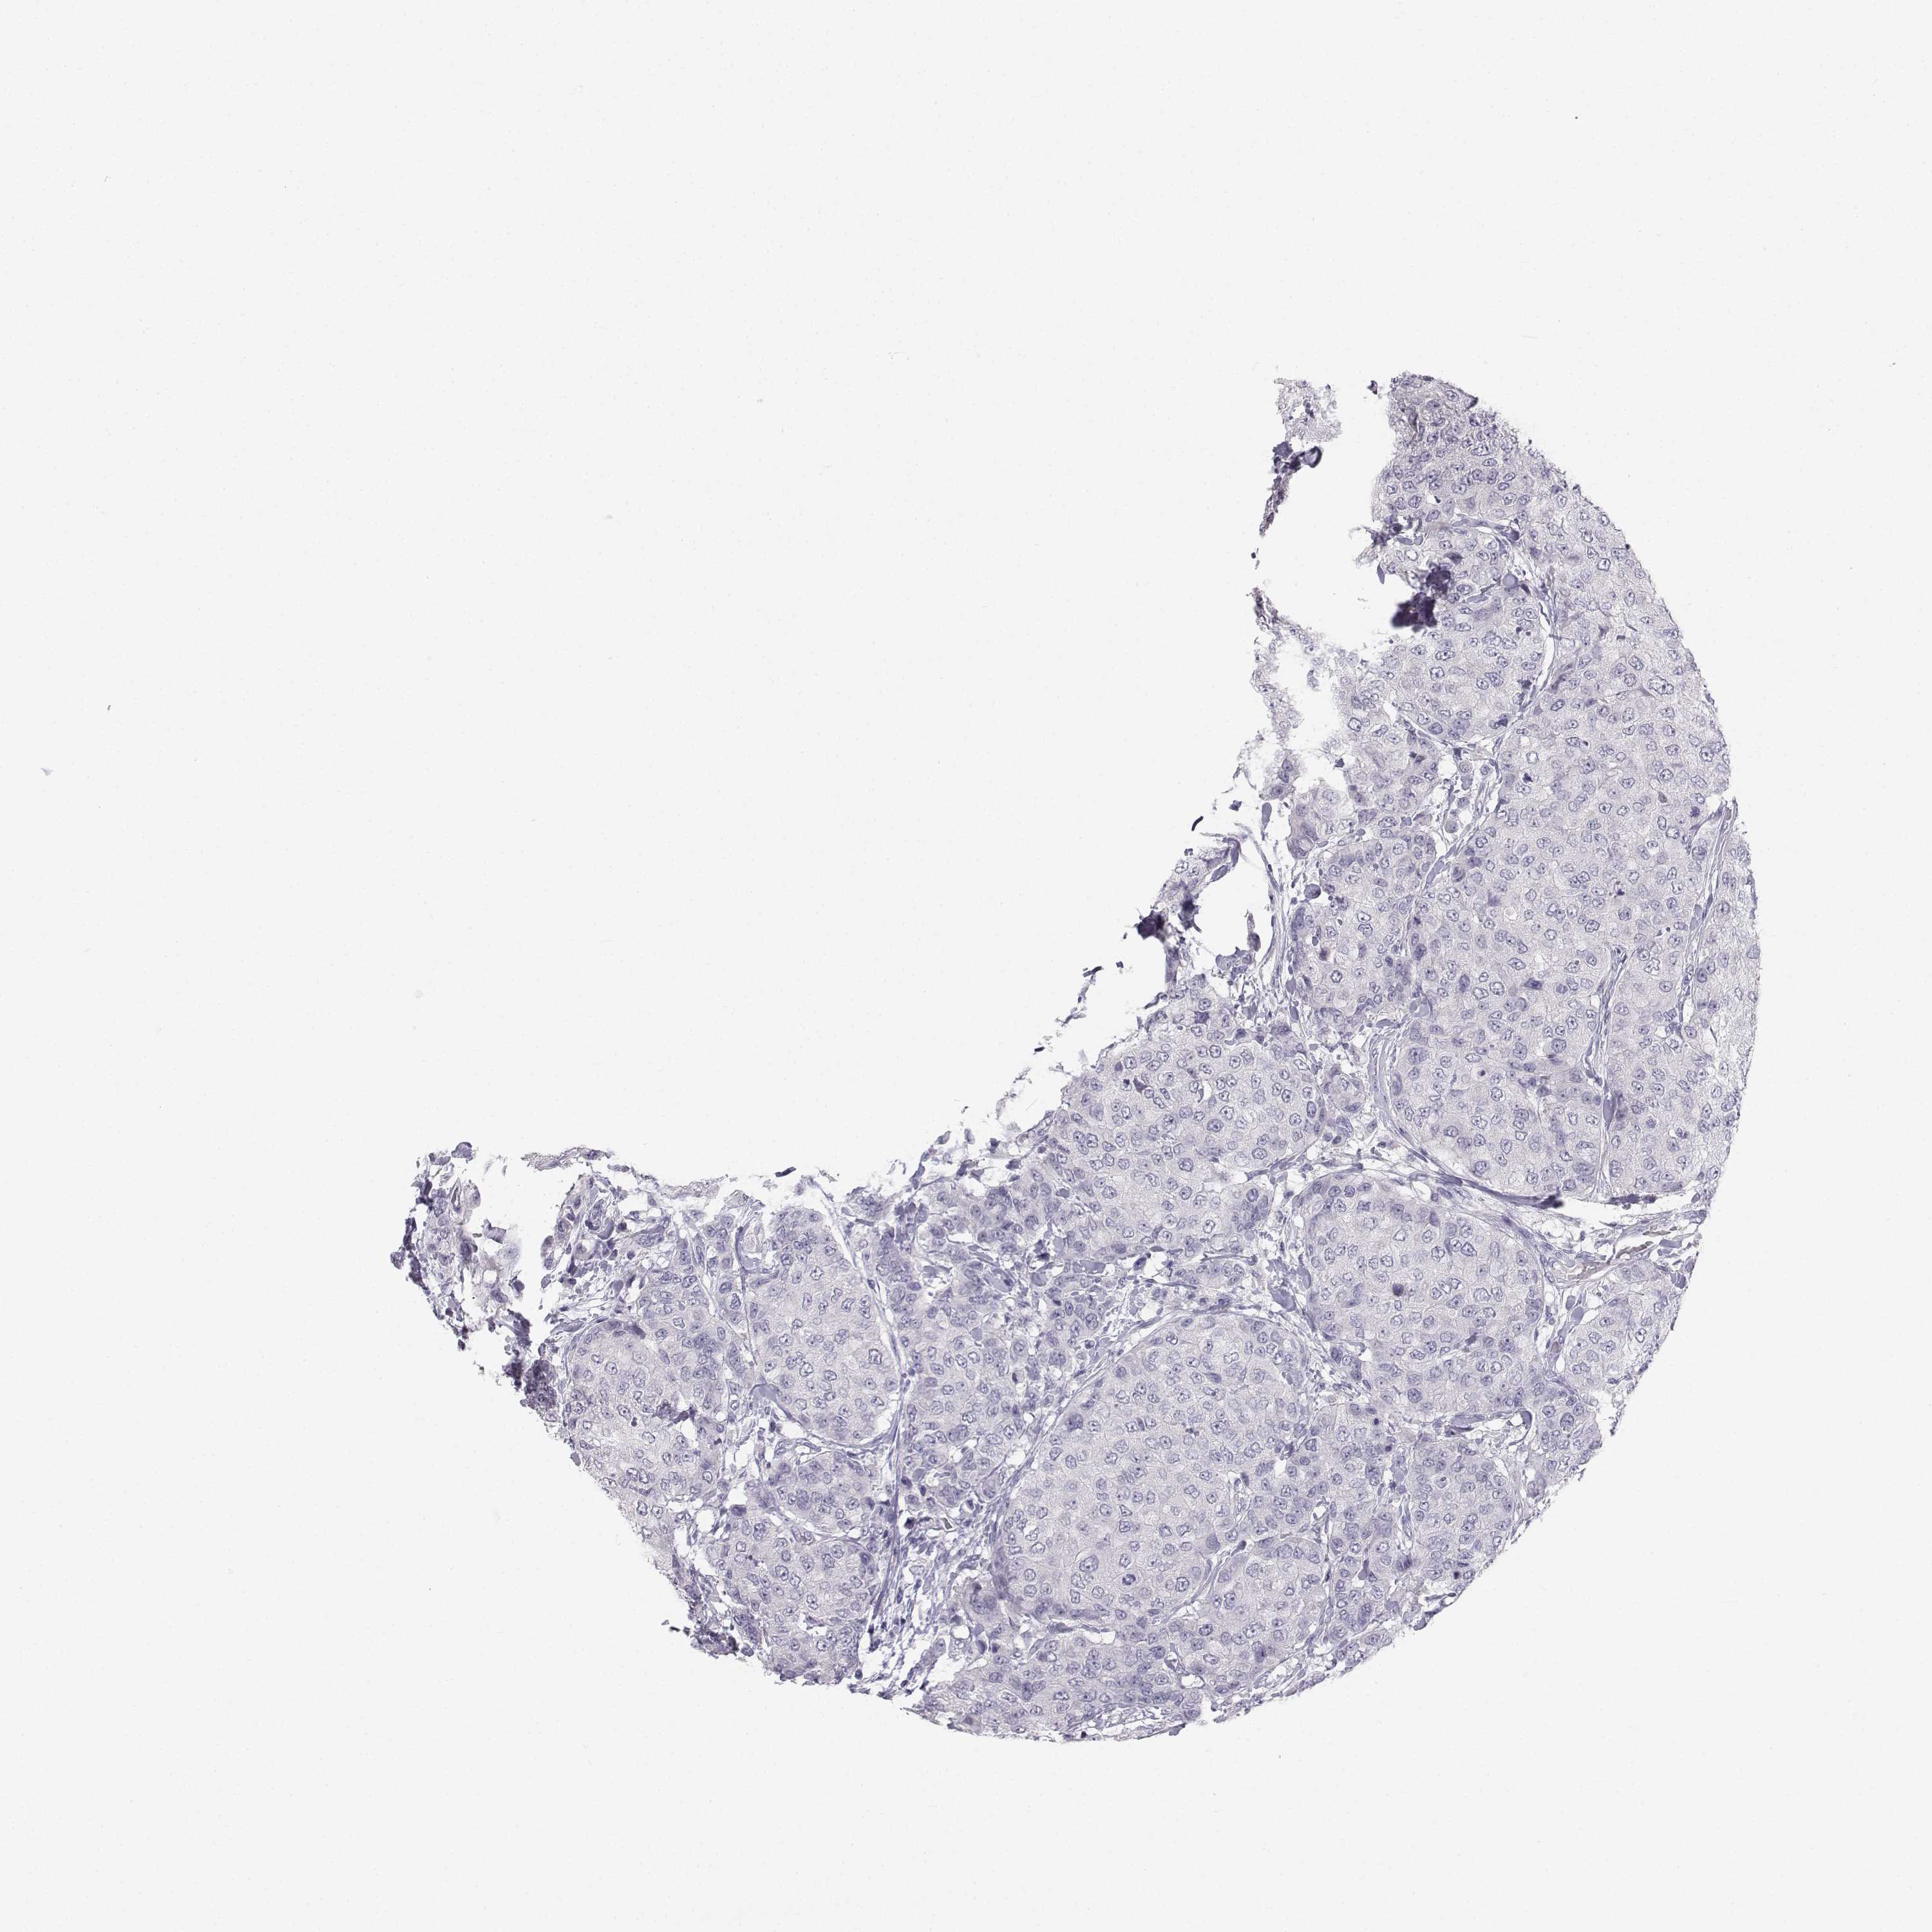

CANCER BREAST CANCER Show tissue menu

BRCA TCGA BRCA VALIDATION PROTEIN EXPRESSION